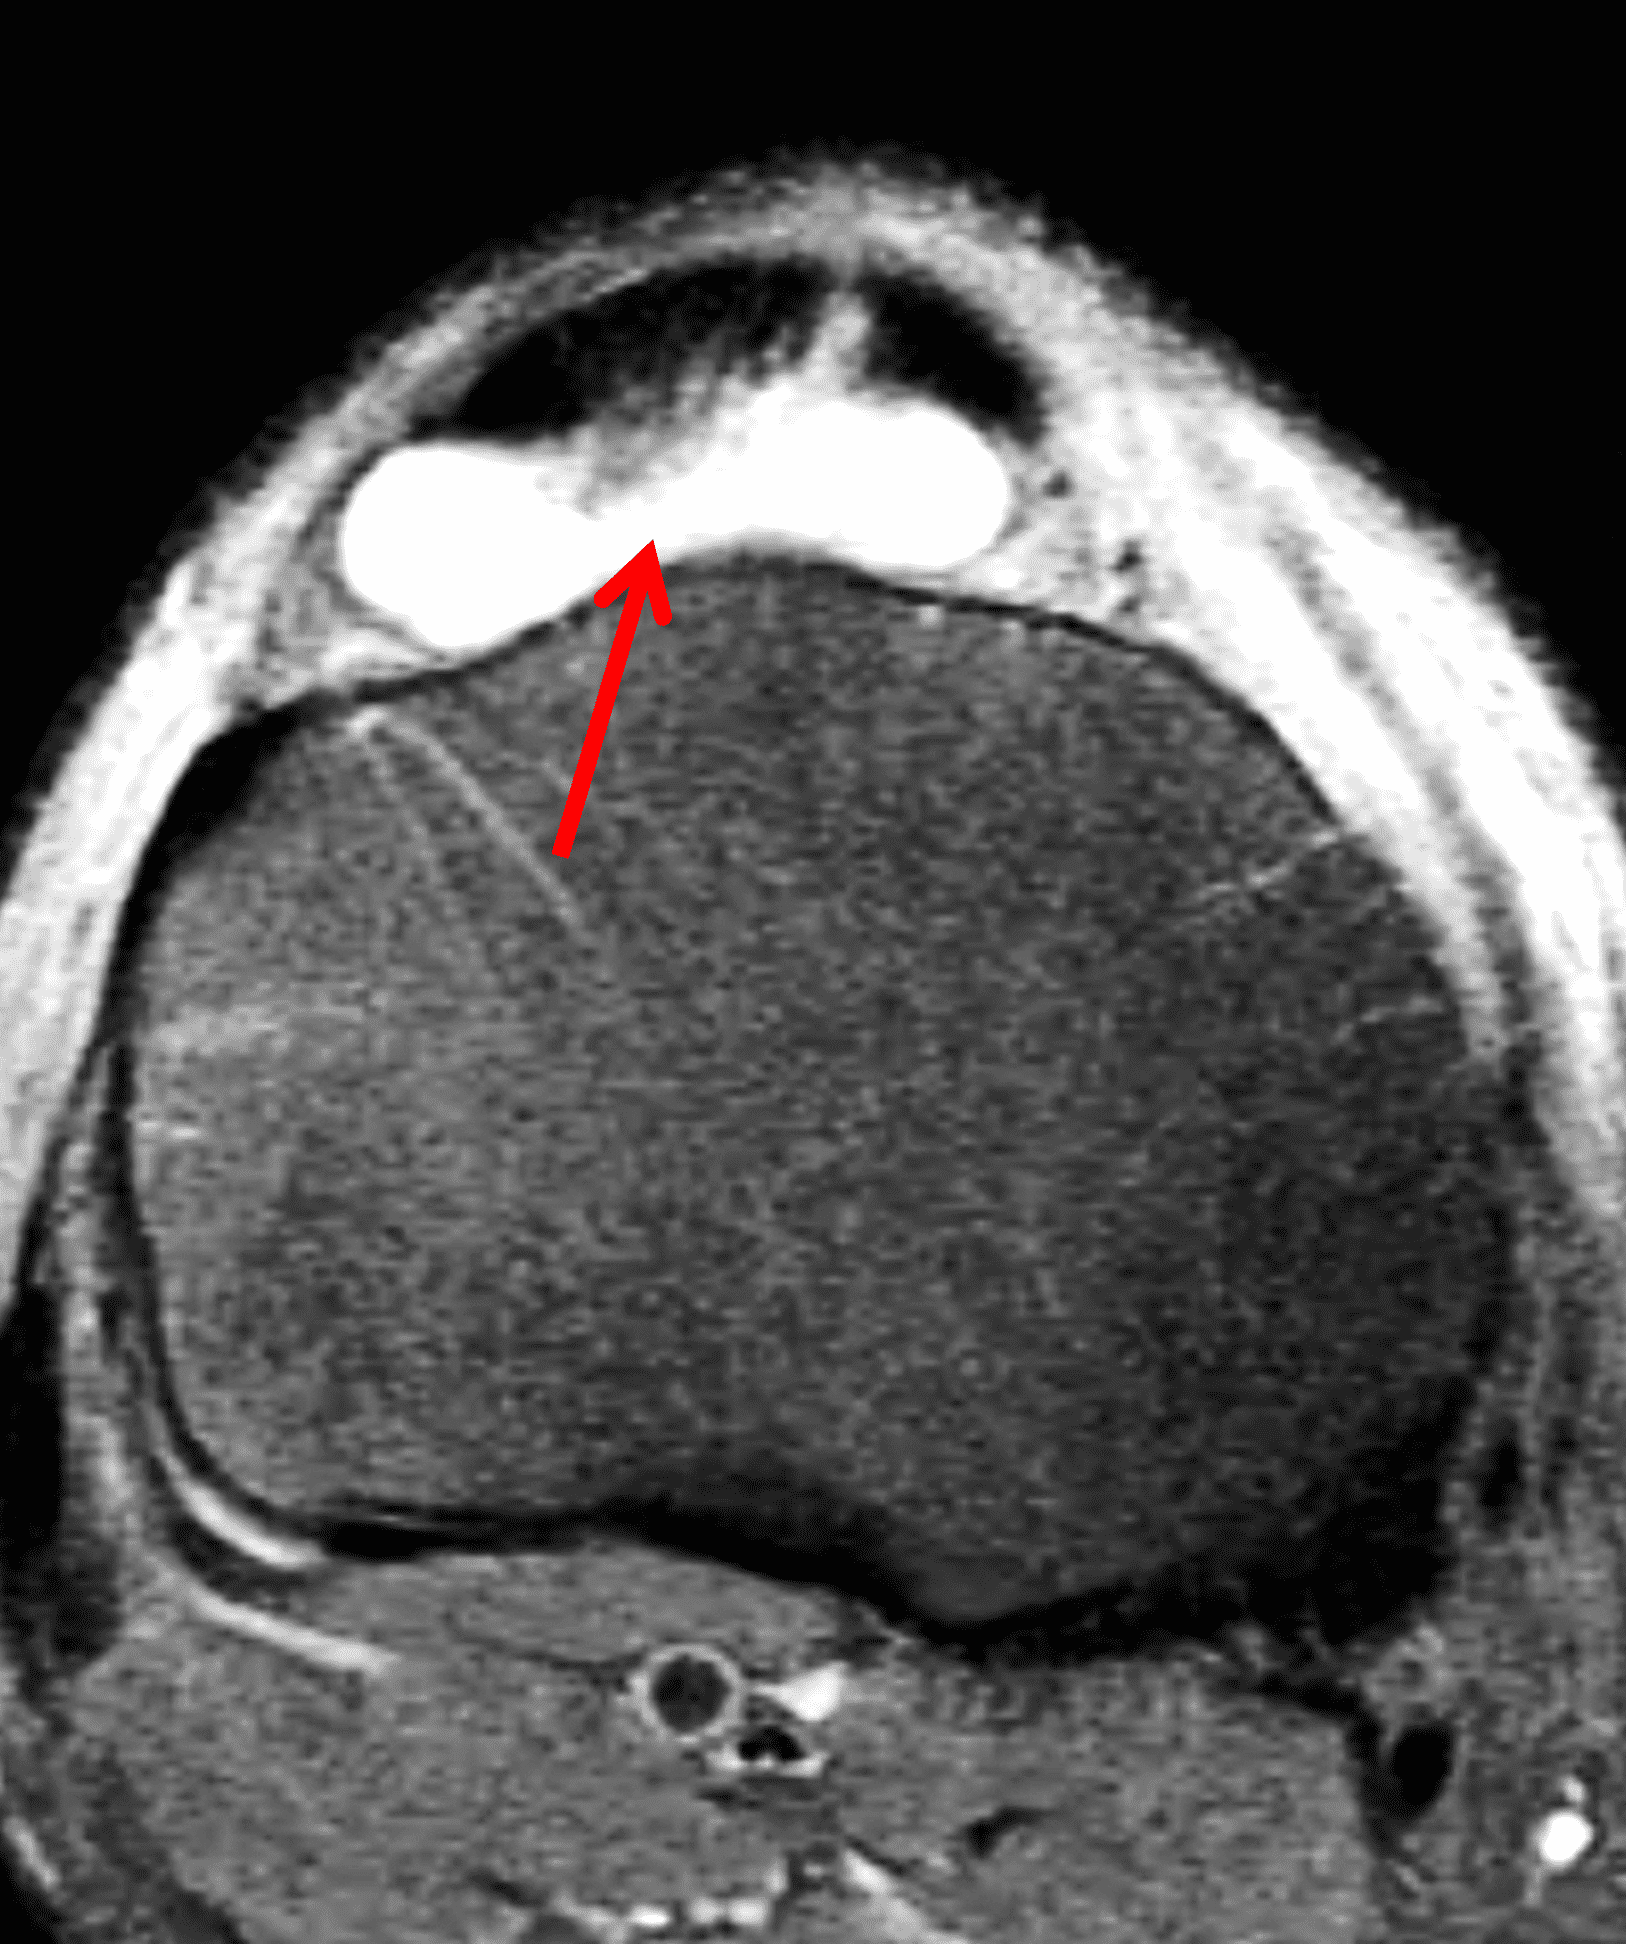

Figure 2: (2A) The coronal image shows a large effusion and severe hypertrophic synovitis (asterisks) in the knee. (2B) On the sagittal image the hypertrophic synovium (asterisks) involves the suprapatellar and infrapatellar recesses as well as the anterior and posterior intercondylar notch. A reactive lymph node (arrow) is present in the popliteal fossa. (2C) The axial image demonstrates myositis (arrows) involving the popliteus and peroneus longus muscles. Note the preserved articular cartilage, lack of erosions, and the absence of subcutaneous or marrow edema.

The causative spirochete invades the synovium, triggering a host inflammatory response that leads to synovial hypertrophy and inflammation, resulting in the characteristic clinical symptoms and imaging findings associated with Lyme arthritis.2 Common MR findings associated with Lyme arthritis include synovitis, joint effusion, popliteal lymphadenopathy, and myositis predominantly involving the popliteus (Figure 4).2,3,9 In contrast to acute septic arthritis due to more common bacteria, subcutaneous edema, marrow edema, erosions, and osteomyelitis are uncommon (Figure 4C).

Figure 4: Lyme arthritis. Fat-suppressed, fluid-sensitive images. (4A) Transverse image shows severe proliferative synovitis in the anterior and posterior joint recesses (arrows). Note the lack of surrounding subcutaneous edema. (4B) In addition to synovitis, the sagittal image shows multiple reactive lymph nodes (red arrows) and popliteal myositis (white arrow). (4C) Coronal image also shows patchy non-joint centered marrow edema in the distal femur and proximal tibia (asterisks), which is uncommon in Lyme disease compared to acute septic arthritis.